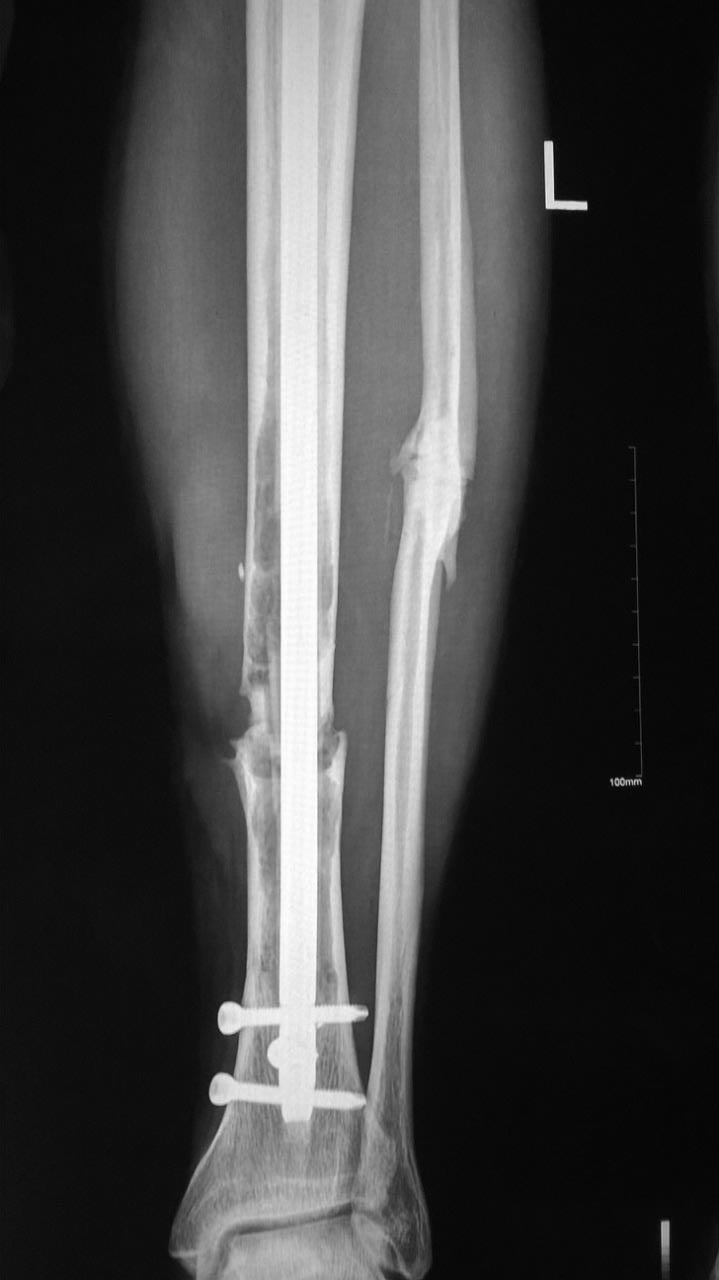

Пациенту 30 лет 3 года назад выполнен остеосинтез открытого (IIIa)

степени перелома большеберцовой кости интрамедуллярным стержнем. В

настоящее время при рентгенографии картина несращения большеберцовой

кости (см. снимки).

На снимках смущает истончение кортикального слоя на большеберцовой

кости, более протяженное в проксимальном отломке.